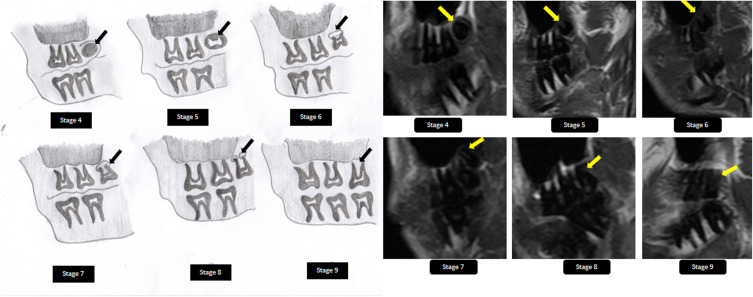

Introduction: Dental age estimation using third molars is a reliable method for estimating the age of individuals. Recently, magnetic resonance imaging (MRI) of the head and neck has been found to be applicable for age estimation of third molar teeth. In the present study, we aimed to apply the Modified Demirjian method of age estimation to magnetic resonance (MR) image sections for dental age estimation by determining the mineralization patterns of the maxillary third molars.

Methods: MRI scans of the patients were performed using SIGNA™ 3.0Tesla MRI GE Healthcare (Chicago, USA) with a moving, multifunctional coil. Two expert radiologists with more than three years of experience independently analyzed the image sections using the open-source Digital Imaging and Communications in Medicine (DICOM) viewer software. The age and sex of the patients whose images were included in the study were recorded using a specially designed proforma. The stage of development of the maxillary third molars was determined using the modified Demirjian method. Inter observer agreement was calculated using the intra class correlation coefficient. Simple linear regression analysis was used to predict the actual age at the third molar development stage.

Results: There was excellent agreement between observers (ICC =0.99 (95% CI = 0.98-0.99)). There was also a significant association between the maxillary third molar tooth development stage and chronological age of the individual (P=0.001; B=1.54; 95% CI = 0.71-2.37).

Discussion: The findings from the present study establish that the Modified Demirjian method can also be reliably applied for dental age assessment in MR sections.